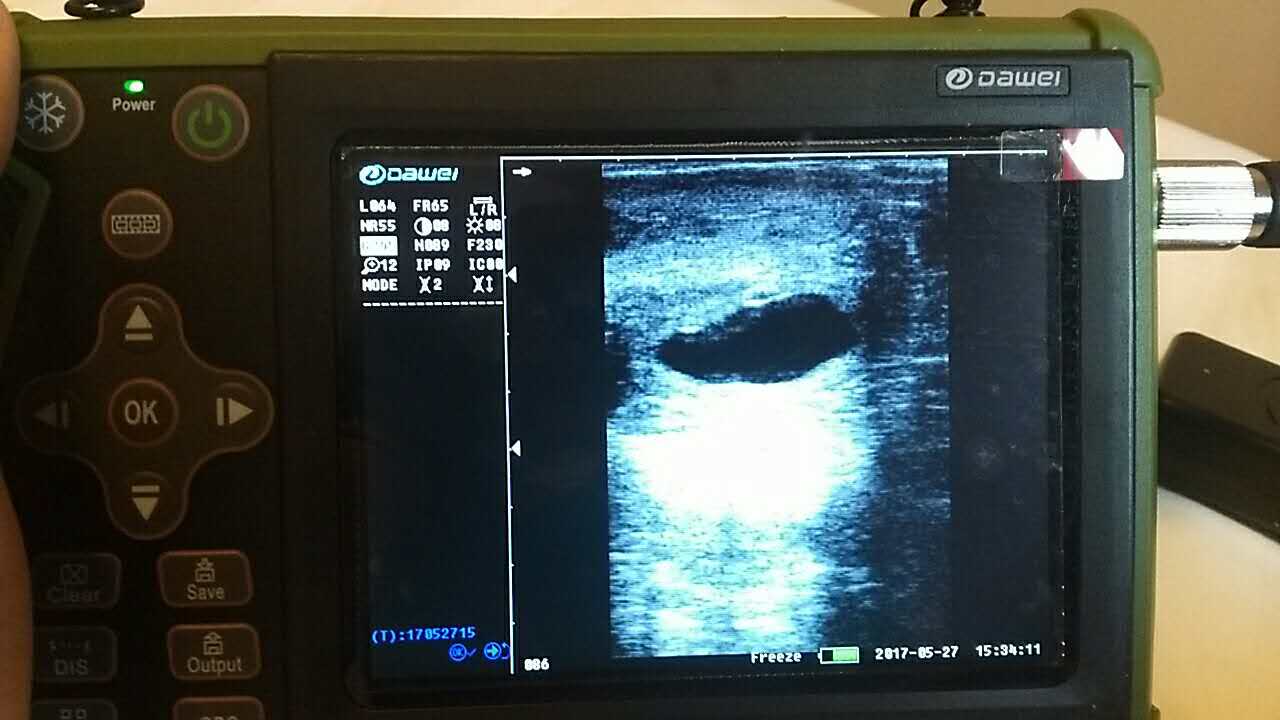

| 羊場(chǎng)母羊照B超辨受孕促增產(chǎn) |

養(yǎng)殖基地140只生產(chǎn)母羊集體接受了B超檢查,利用現(xiàn)代化技術(shù)方法,解決生產(chǎn)母羊繁育難題促進(jìn)畜牧業(yè)生產(chǎn)結(jié)構(gòu)的調(diào)整。 在檢查中,技術(shù)人員拿著B超儀器,給生產(chǎn)母羊做免費(fèi)受孕普查。用B超檢測(cè)母羊受孕情況,用這種方法給母羊做檢測(cè)可以準(zhǔn)確掌握母羊是否受孕、母羊生產(chǎn)周期。通過(guò)B超早期孕檢和生殖系統(tǒng)疾病診斷,可以清晰的觀測(cè)到生產(chǎn)的宮腔和胎兒的生產(chǎn)發(fā)育情況。除了幫助基地對(duì)問(wèn)題羊做出正確診斷,提出合理的治療方案,淘汰無(wú)治療價(jià)值的長(zhǎng)期空懷羊,還能提高受孕率,降低飼養(yǎng)成本,有效規(guī)避了假妊娠造成的經(jīng)濟(jì)損失。

檢測(cè)懷孕 估測(cè)胎仔數(shù) 疾病診斷 胎兒活力鑒定 胎心搏動(dòng) 適用對(duì)象:適用于羊、豬、狗等動(dòng)物受孕診斷(集成6種常見(jiàn)動(dòng)物孕周測(cè)量數(shù)據(jù)包) 適用范圍:規(guī)模化豬場(chǎng),人工授精站,飼料/獸藥經(jīng)銷商及企業(yè),科研教學(xué)單位 |